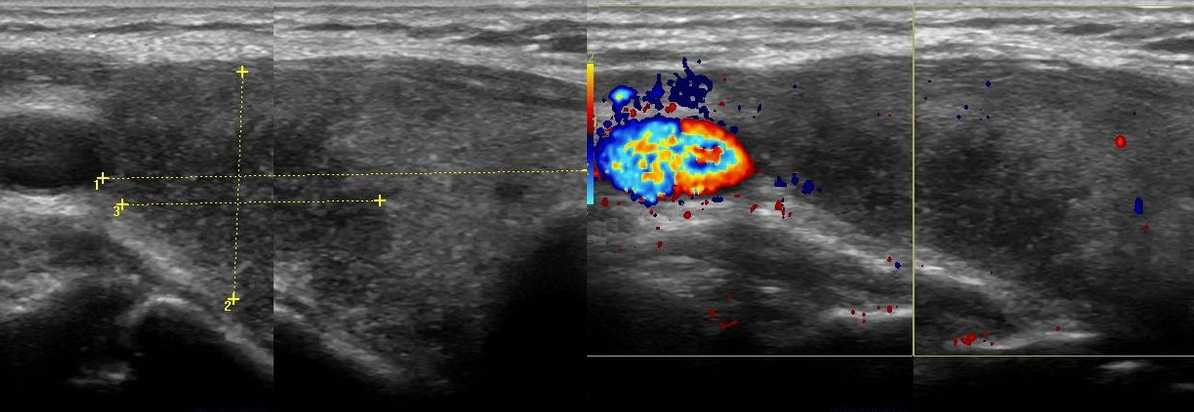

Подострый тиреоидит де Кервена на УЗИ

Подострый тиреоидит де Кервена — негнойное воспаление щитовидной железы после перенесенной вирусной инфекции (грипп, корь, паротит и др.). На фоне температуры в нижнем отделе шеи определяется болезненная припухлость. В начале заболевания воспалительный процесс локализуется в одной доле, затем захватывает всю железу — «ползущий тиреоидит». Первоначально появляется тиреотоксикоз, а затем гипотиреоз. Могут отмечаться общие аутоиммунные реакции. Спустя несколько недель подострый тиреоидит разрешается спонтанно, обычно без нарушений функции щитовидной железы. Нестероидные противовоспалительные препараты и кортикостероиды часто могут купировать состояние за 24 часа.

При тиреоидите де Кервена щитовидная железа диффузно или локально увеличена; в области наибольшей болезненности определяются крупные гипоэхогенные участки неправильной формы с размытыми границами (наиболее выражено снижение эхогенности в центре «пятна»), кровоток в аномальной зоне почти отсутствует; часто увеличены региональные лимфоузлы. Наличие гиперэхогенных структур не характерно. В процессе рубцевания поврежденная ткань может замещаться фиброзной, но в большинстве случаев восстанавливается нормальная структура железы.

Рисунок. Пожилая женщина с жалобами на подъемы температуры и болезненную припухлость внизу шеи. На УЗИ щитовидная железа увеличена, в правой доле определяется крупная гипоэхогенная зона неправильной формы, с размытыми границами, без кровотока. При динамическом наблюдении очаг увеличивался в размерах, а так же появились гипоэхогенные участки в левой доле. Заключение: Подострый тиреоидит де Кервена.

Рисунок. Женщина 43-х лет с болезненной и плотной «опухолью» внизу шеи. На УЗИ щитовидная железа диффузно увеличена, контур волнистый, гипоэхогенные зоны неправильной формы, без четких границ, кровоток на гипоэхогенных участках понижен. Заключение: Подострый тиреоидит де Кервена. Спустя 1 год (внизу) щитовидная железа уменьшилась, паренхима нормальной эхогенности, однородная.

Рисунок. На УЗИ в правой доле щитовидной железы в области максимальной болезненности определяется крупный гипоэхогенный участок неправильной формы, без четких границ, кровоток в аномальной зоне отсутствует. Шейные лимфоузлы увеличены, гипоэхогенные, округлые. Заключение: Подострый тиреоидит де Кервена. При такой ультразвуковой картине необходима дифференциальная диагностика с карциномой щитовидной железы.